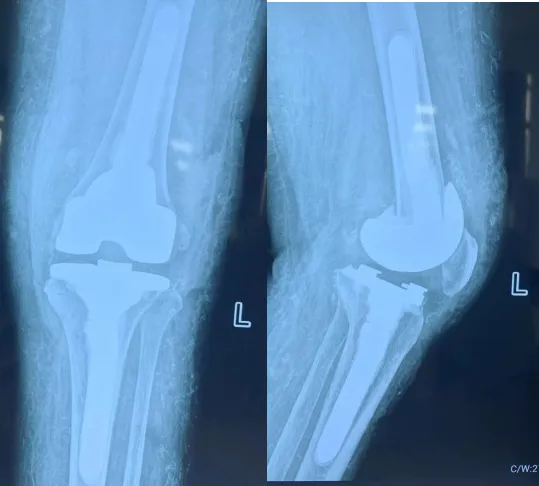

膝关节假体选择

患者内翻、屈曲挛缩、脱位。

膝关节复位后软组织张力大,假体局部应力大,常规假体极易出现松动,必须选择加延长杆的半限制性假体。

术中,保留了骨量,平衡了软组织,重要的是膝关节基本达到伸直(欠15度),下肢力线良好。